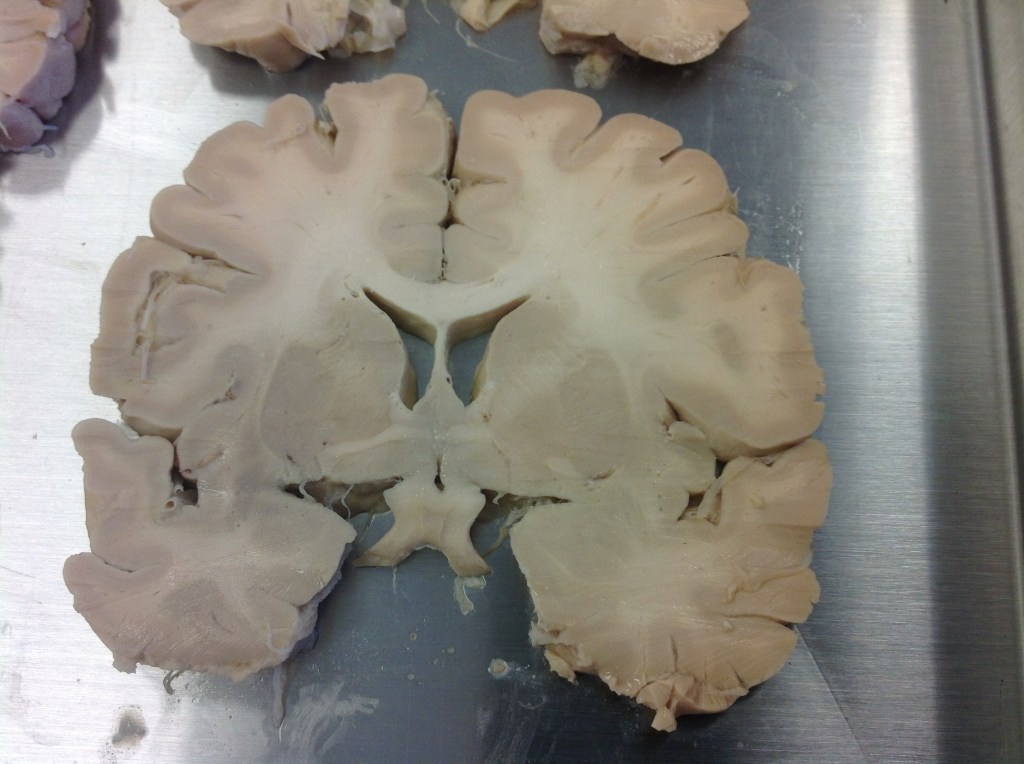

A coronal cut through the brain. The dark structures in the center are components of the basal ganglia

The dark or gray matter around the periphery of the brain in this photo is the six layered cortex where the neuron cell bodies reside